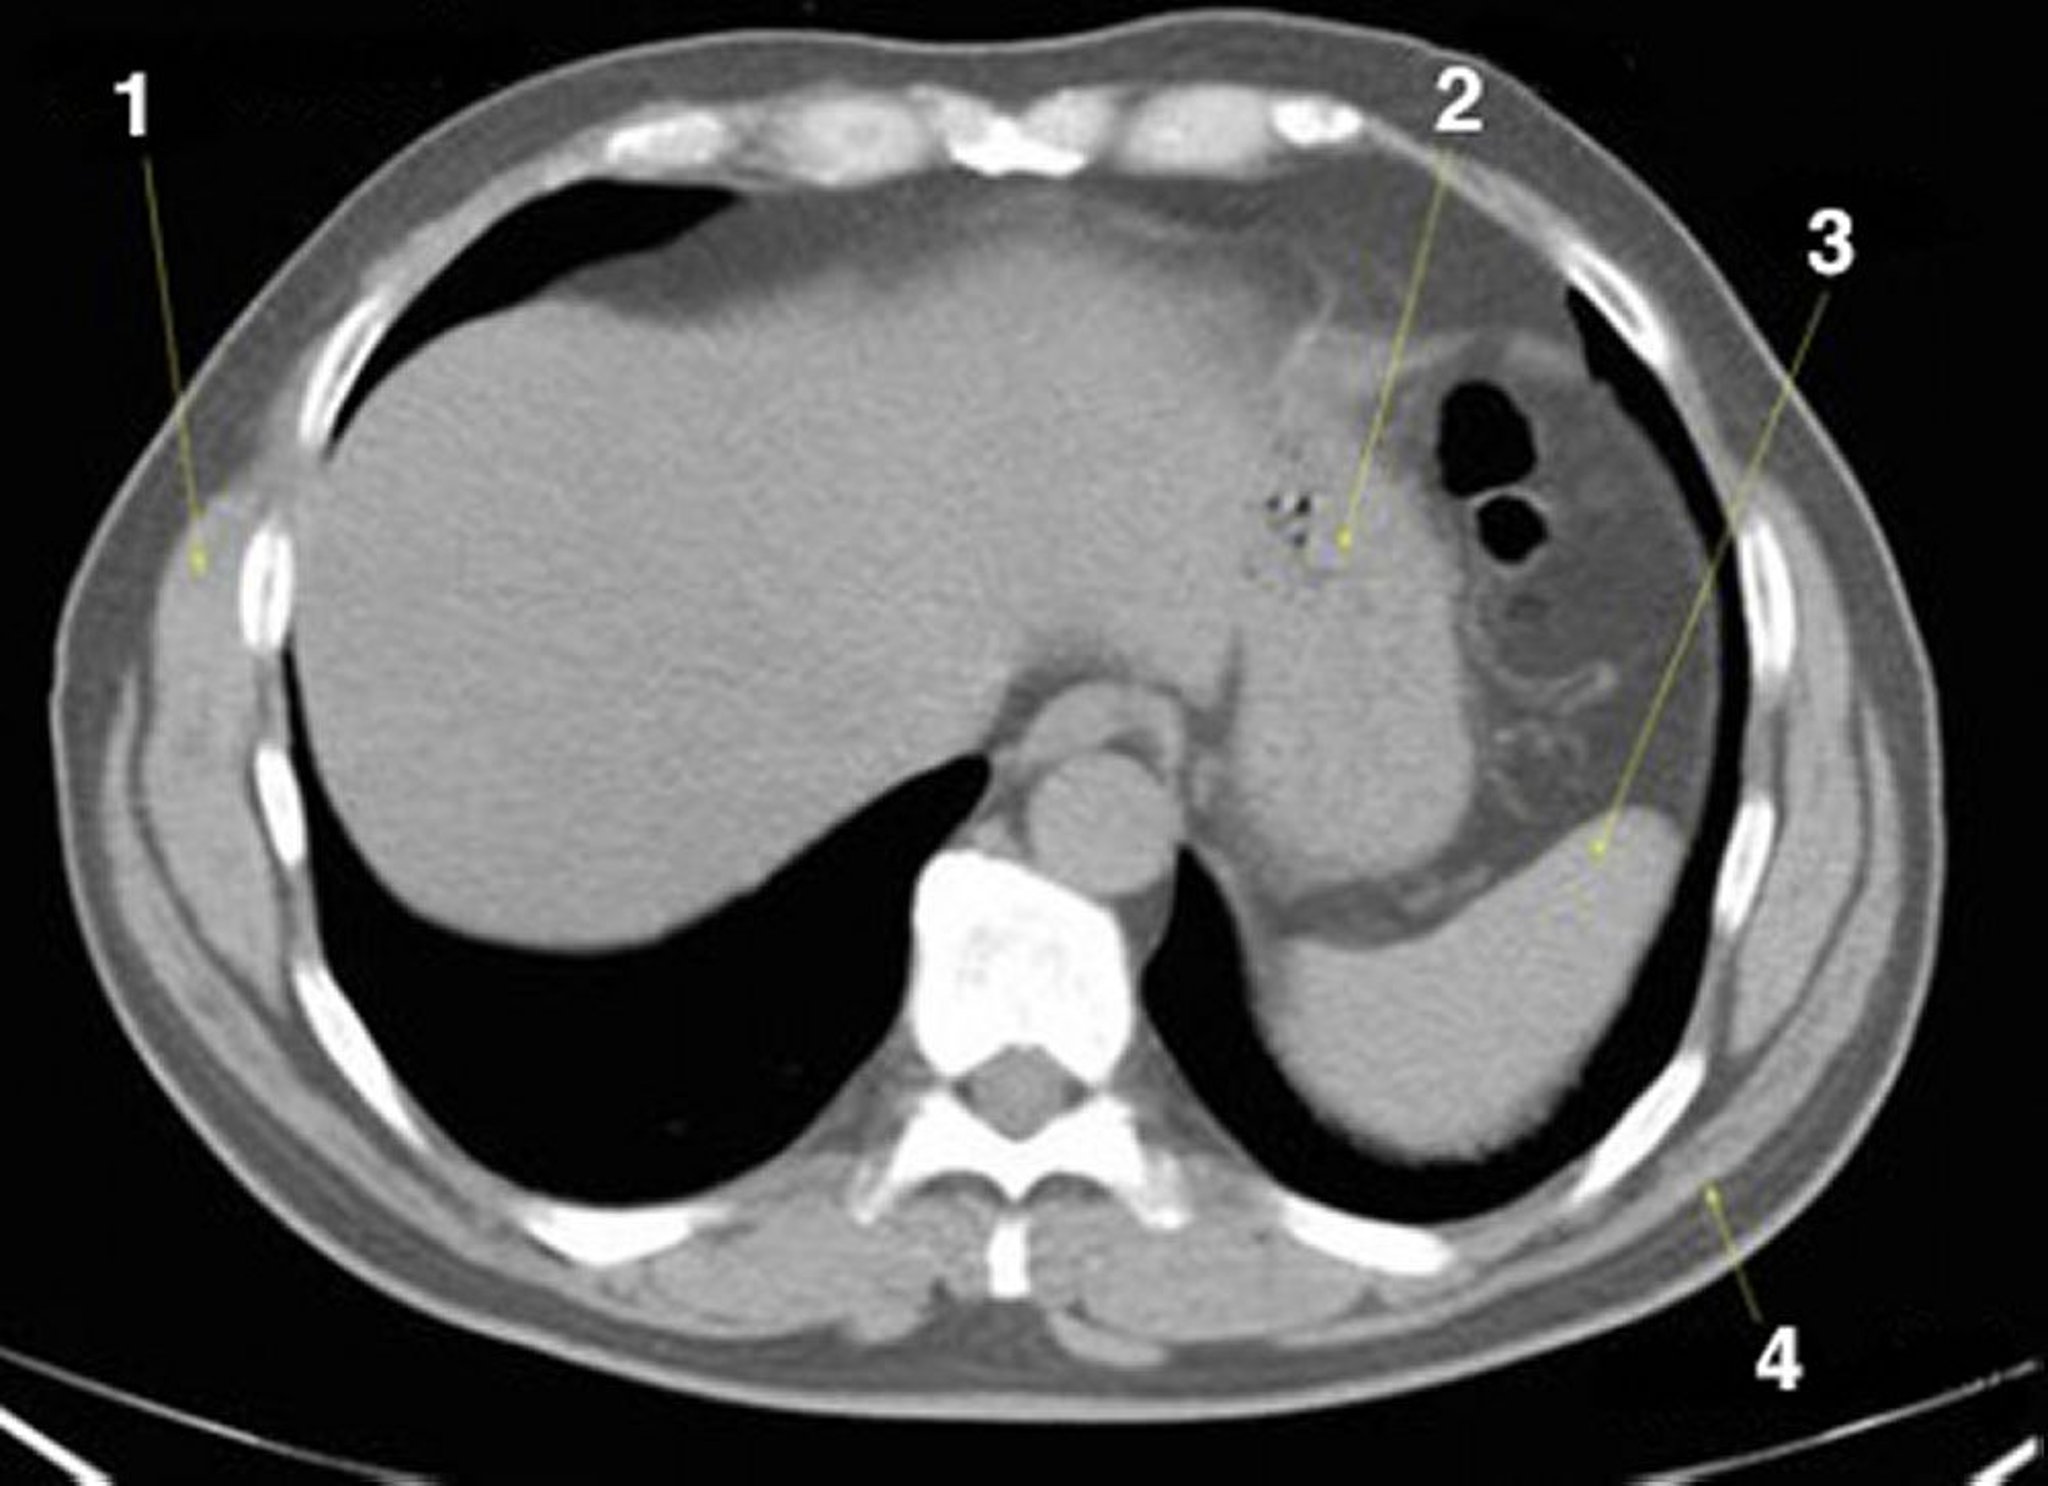

Tomografía computarizada sin contraste de abdomen y pelvis que muestra anatomía normal (corte 2)

1 = serrato anterior; 2 = estómago; 3 = bazo; 4 = dorsal ancho.